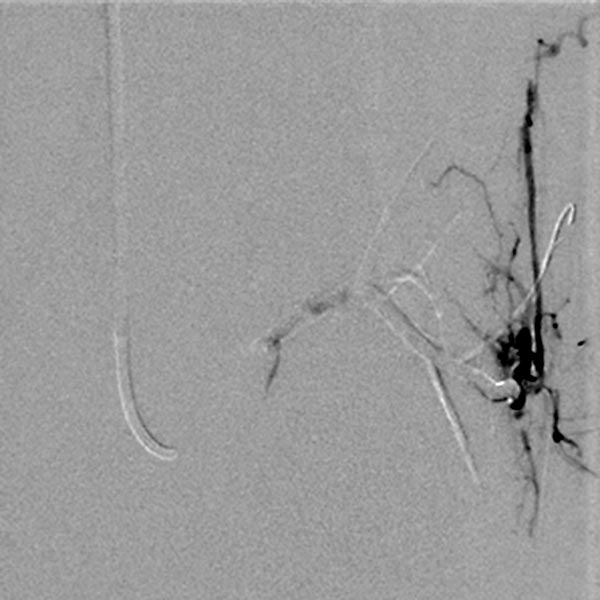

Superselective digital subtraction angiography via a microcatheter in the superior gluteal artery in a distal branch. The nidus of the fine fistulous arteriovenous malformation shows such fine shunts that they can hardly be resolved anatomically on angiography.

During embolization via the microcatheter (not shown) using the roadmap technique, the embolic agent (ethylene-vinyl alcohol copolymer) is pushed forward into the nidus and further into the venous outflow of the AVM to close even the smallest fistulas ("plug & push" technique).